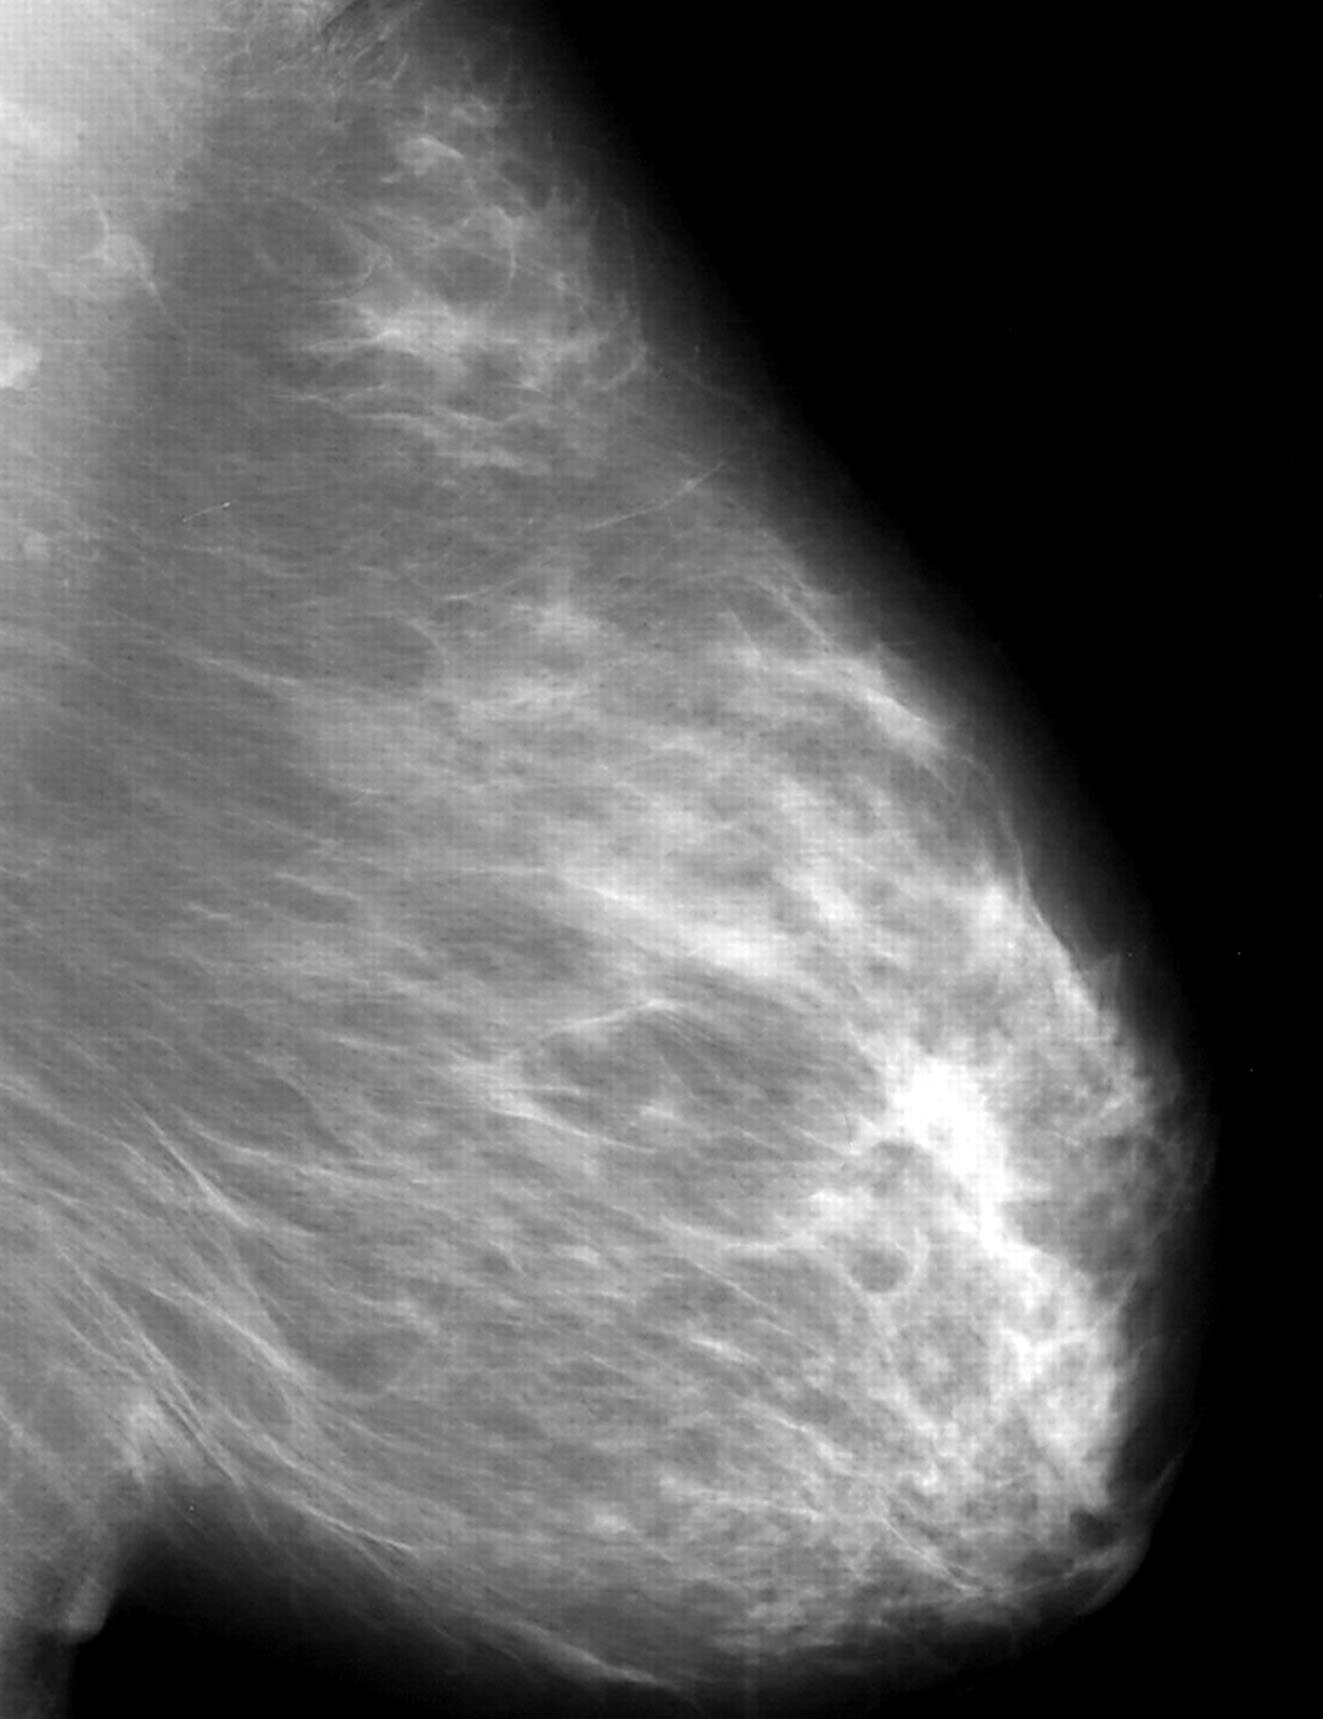

Radiology description

- Mammographically often presents as a spiculated mass with or without calcifications but may present as an architectural distortion or calcifications alone

- Targeted ultrasonography often used to enhance visualization

- MRI often shows enhancing mass lesion with variable washout kinetic patterns (Breast J 2010;16:394)

- MRI is sensitive but nonspecific technique is reserved for screening patients at high risk (e.g., BRCA mutation carriers), patients with dense breast tissue, estimating extent of disease in patients with lobular carcinoma, evaluating response to neoadjuvant chemotherapy or evaluating indeterminate abnormalities on mammography / ultrasound (Breast 2013;22:S77)